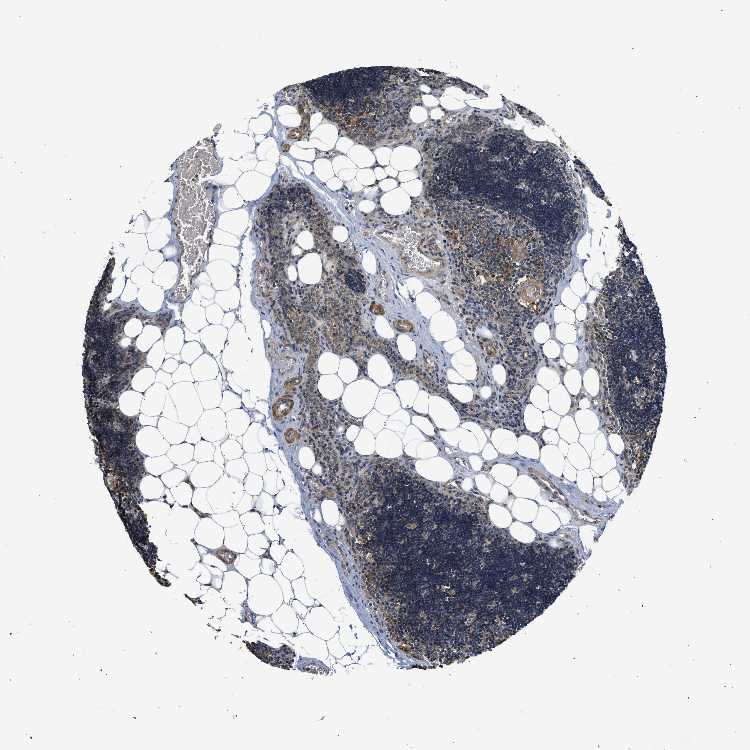

TISSUE PRIMARY DATA LYMPH NODE Show tissue menu

Lymph node

LYMPH NODE - Antibody stainingi

Antibody staining in the annotated cell types in the current human tissue is reported as not detected, low, medium, or high, based on conventional immunohistochemistry profiling in selected tissues. This score is based on the combination of the staining intensity and fraction of stained cells.

Each image is clickable and will lead to virtual microscopy that enables deeper exploration of all samples and also displays staining intensity scores, fraction scores and subcellular localization as well as patient and tissue information for each sample.

Antibody HPA020338

Germinal center cells Not detected

Non-germinal center cells Low